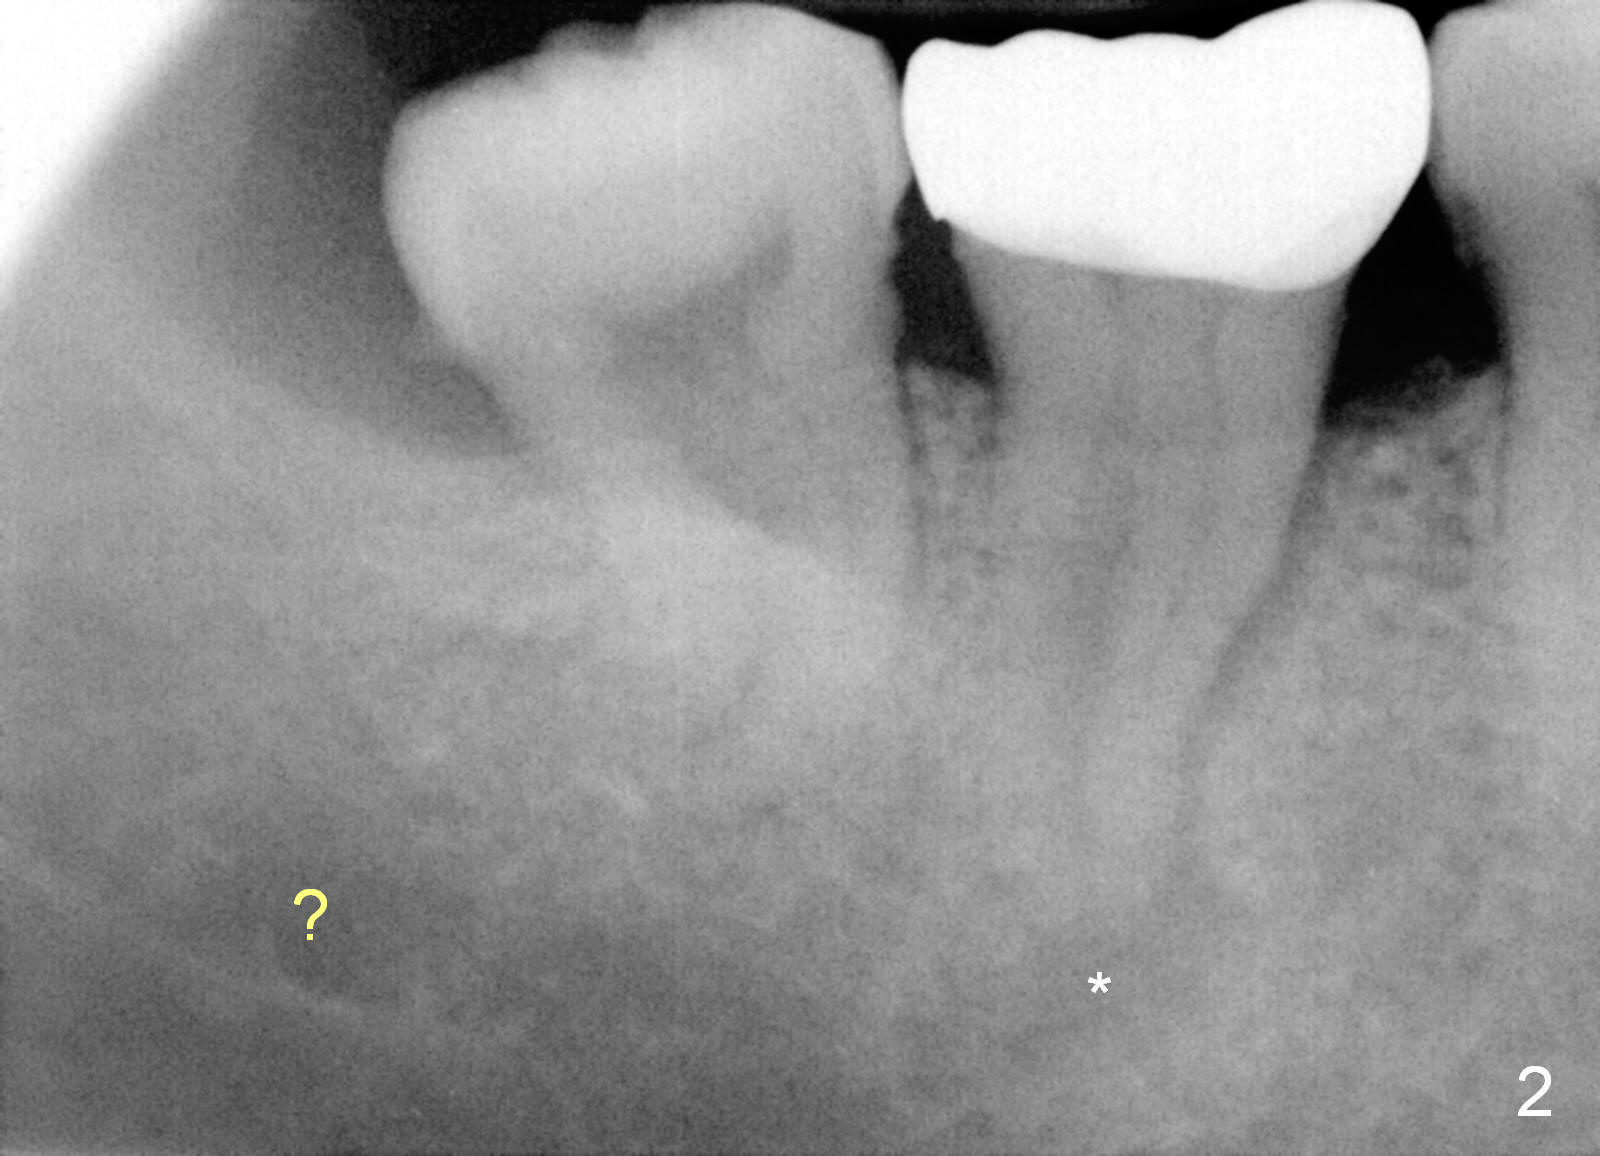

A 69-year-old lady has pain at #31. Because of curved and obliterated root canals (Fig.1,2), it is the better to extract the tooth and have an immediate implant. The roots are also long and narrow and close to the Inferior Alveolar Canal (Fig.1 yellow dashed line), whereas the canal is hardly recognizable in a 2nd PA (Fig.2 ?). For safety, taps are to be used for osteotomy (Fig.3).